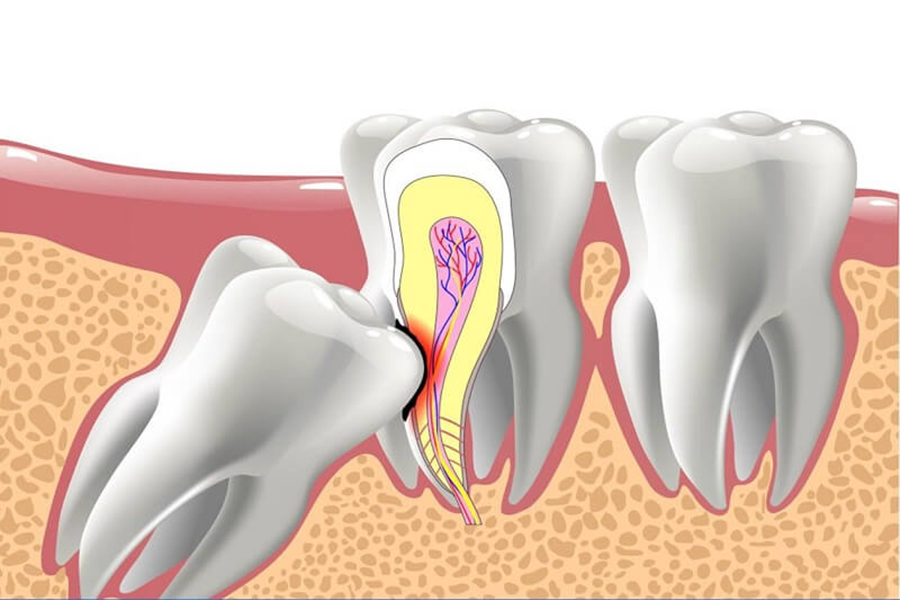

Trung tâm nha khoa thẩm mỹ kỹ thuật cao NHA KHOA PHÁP VIỆT Chuyên cung cấp các dịch vụ nha khoa điều trị, phòng ngừa, và các dịch vụ nha khoa thẩm mỹ phục hình răng sứ cao cấp, chỉnh hình răng hô móm, lệch lạc, cắm ghép implant, tẩy trắng răng kỹ thuật cao… Nha khoa Pháp Việt do đội ngũ bác sỹ Răng Hàm Mặt được đào tạo chính quy và đã qua tu nghiệp ở Pháp trực tiếp khám và điều trị. Đặc biệt, chúng tôi luôn luôn miễn phí: Khám và tư vấn về chăm sóc răng miệng Nhổ răng sữa lung lay dùng thuốc tê bôi.

Nha Khoa Pháp Việt với nhiều năm kinh nghiệm trong lĩnh vực điều trị, phòng ngừa và các dịch vụ nha khoa thẩm mỹ phục hình răng sứ cao cấp, chỉnh hình răng hô móm, lệch lạc, cắm ghép implant, tẩy trắng răng kỹ thuật cao,... Với đội ngũ bác sỹ chuyên nghiệp được đào tạo chuyên sâu giúp mang lại cho mọi người tự tin với hàm răng chắc khỏe.